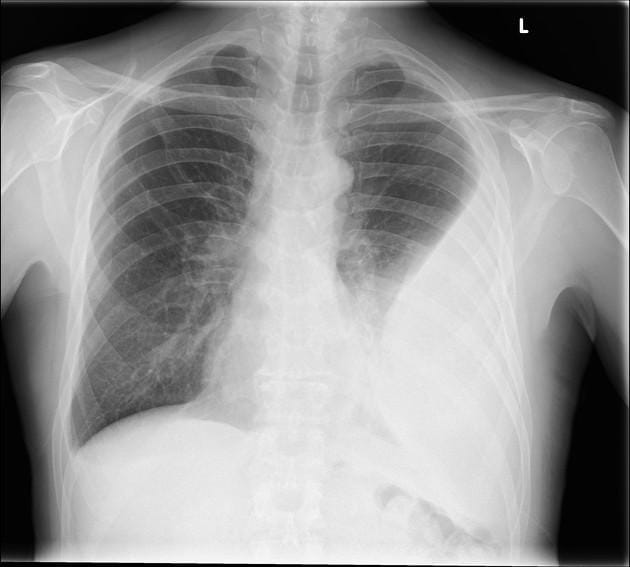

Chest X-ray: Conventional CXR is often the most available imaging modality leading to the identification of a pleural space infection. A minimum of 175 mL of pleural fluid is necessary to result in blunting of the costophrenic angle on a posteroanterior film, although smaller effusions may be identified on a lateral view.